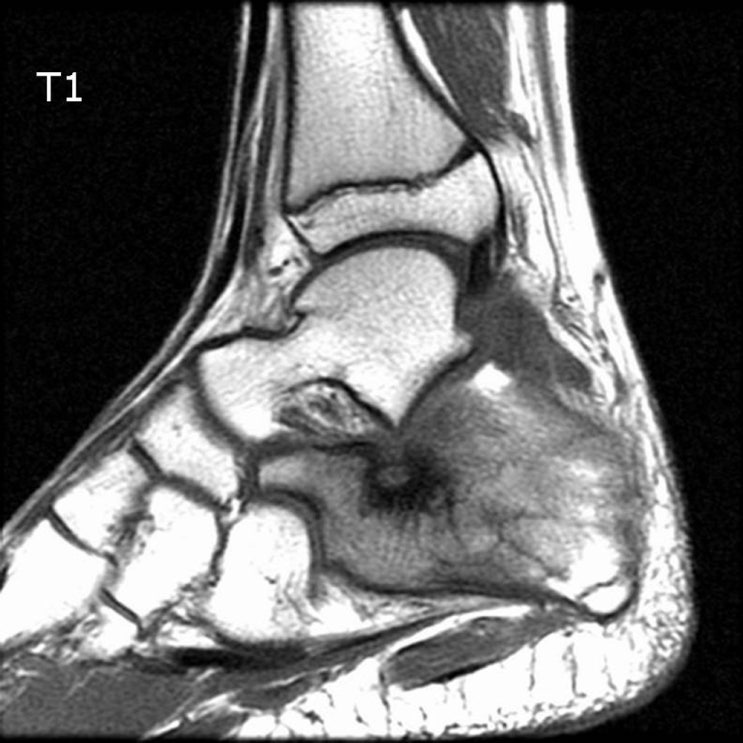

[족부][증례] 소아 osteoid osteoma

DDx : osteomyelitis, stress fracture, inflammatory arthritis, more aggressive bone tumor. M/15 1...